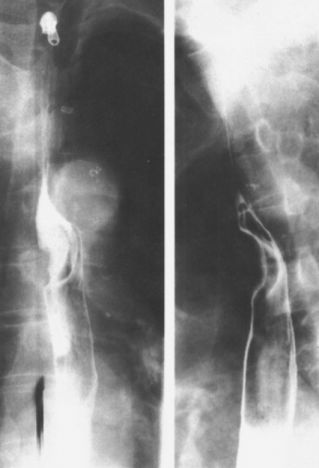

贲门失弛缓:鸟嘴征。

中度贲门失迟缓

重度贲门失迟缓